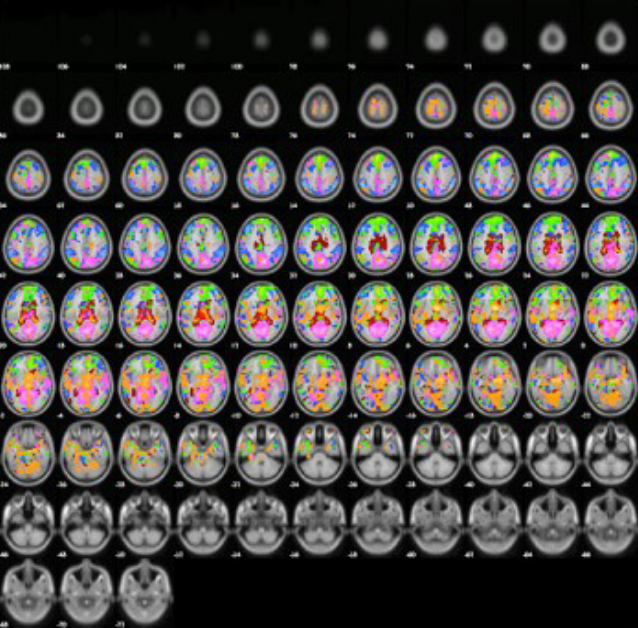

rs-fMRI(resting state fMRI)​

安静時における脳の神経活動を測定する技術です。脳領域間における機能的結合や安静時の神経活動(デフォルトモードネットワークなど)の観察に用いられています。

神経科学や心理学、臨床医学など多くの研究に利用されています。​

安静時における脳領域間の機能的結合を評価しています。(Functional Connectivity)

​アカゲザルの特定の脳領域(**)に対して相関がある脳領域を評価しています。​